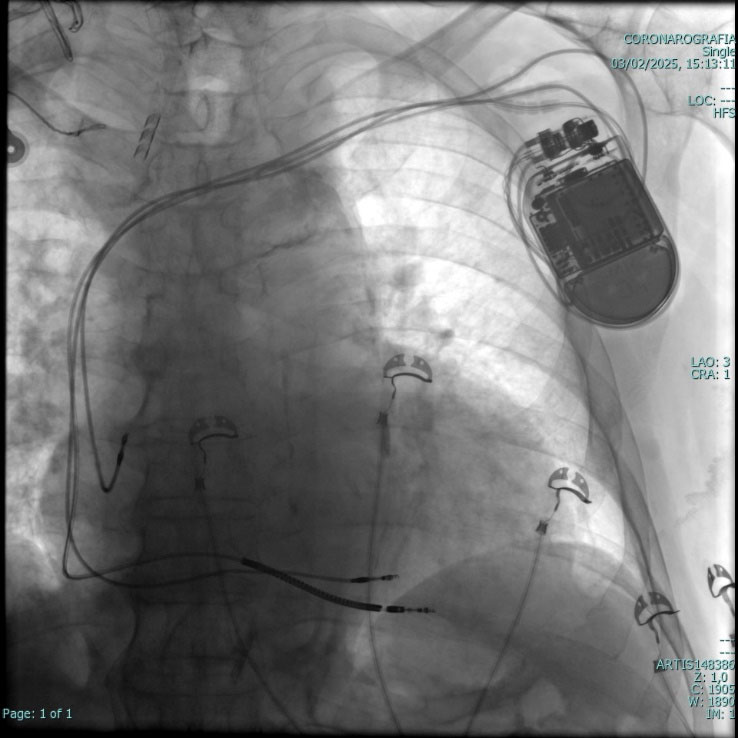

CRT-D E CRT-D CON STIMOLAZIONE DI BRANCA SINISTRA

Nei soggetti colpiti da infarto del miocardico acuto sono frequenti situazioni di scompenso cardiaco. Questo avviene perché l'area interessata dalla necrosi (la zona in cui è avvenuto l'infarto) non si contrae più adeguatamente determinando una grave depressione della funzione di pompa cardiaca chiamata frazione di eiezione (FE). In questa condizione il miocardio non espelle adeguatamente i liquidi depositatisi nei distretti corporei, soprattutto a livello degli alveoli polmonari (edema polmonare). In tali condizioni le quattro camere cardiache non seguono la sequenza normale di contrazione.

Tali difetti o alterazioni possono essere corrette attraverso una terapia di resincronizzazione cardiaca con la stimolazione elettrica del ventricolo sinistro con elettrocateteri che posizionati (per via venosa) attraverso le vene, decorrono sulla superficie del cuore. Si tratta di uno speciale dispositivo (simile al pacemaker, per dimensioni e per tipologia di procesura di impianto sottocutaneo) dotato di tre elettrocateteri che stimolano le camere, con l'obiettivo di ripristinare la normale sequenza delle contrazioni e ottimizzare la funzione cardiaca nei soggetti con insufficienza cardiaca refrattaria alla terapia farmacologica (che in determinate situazioni non consente risultati soddisfacenti).

In alcuni soggetti selezionati che presentano specifiche alterazioni elettrocadiografiche (BBS: blocco di branca sinistra) i sistemi sono integrati con una stimolazione specifica (left bundle branch area pacing, LBBAP) di branca sinistra.